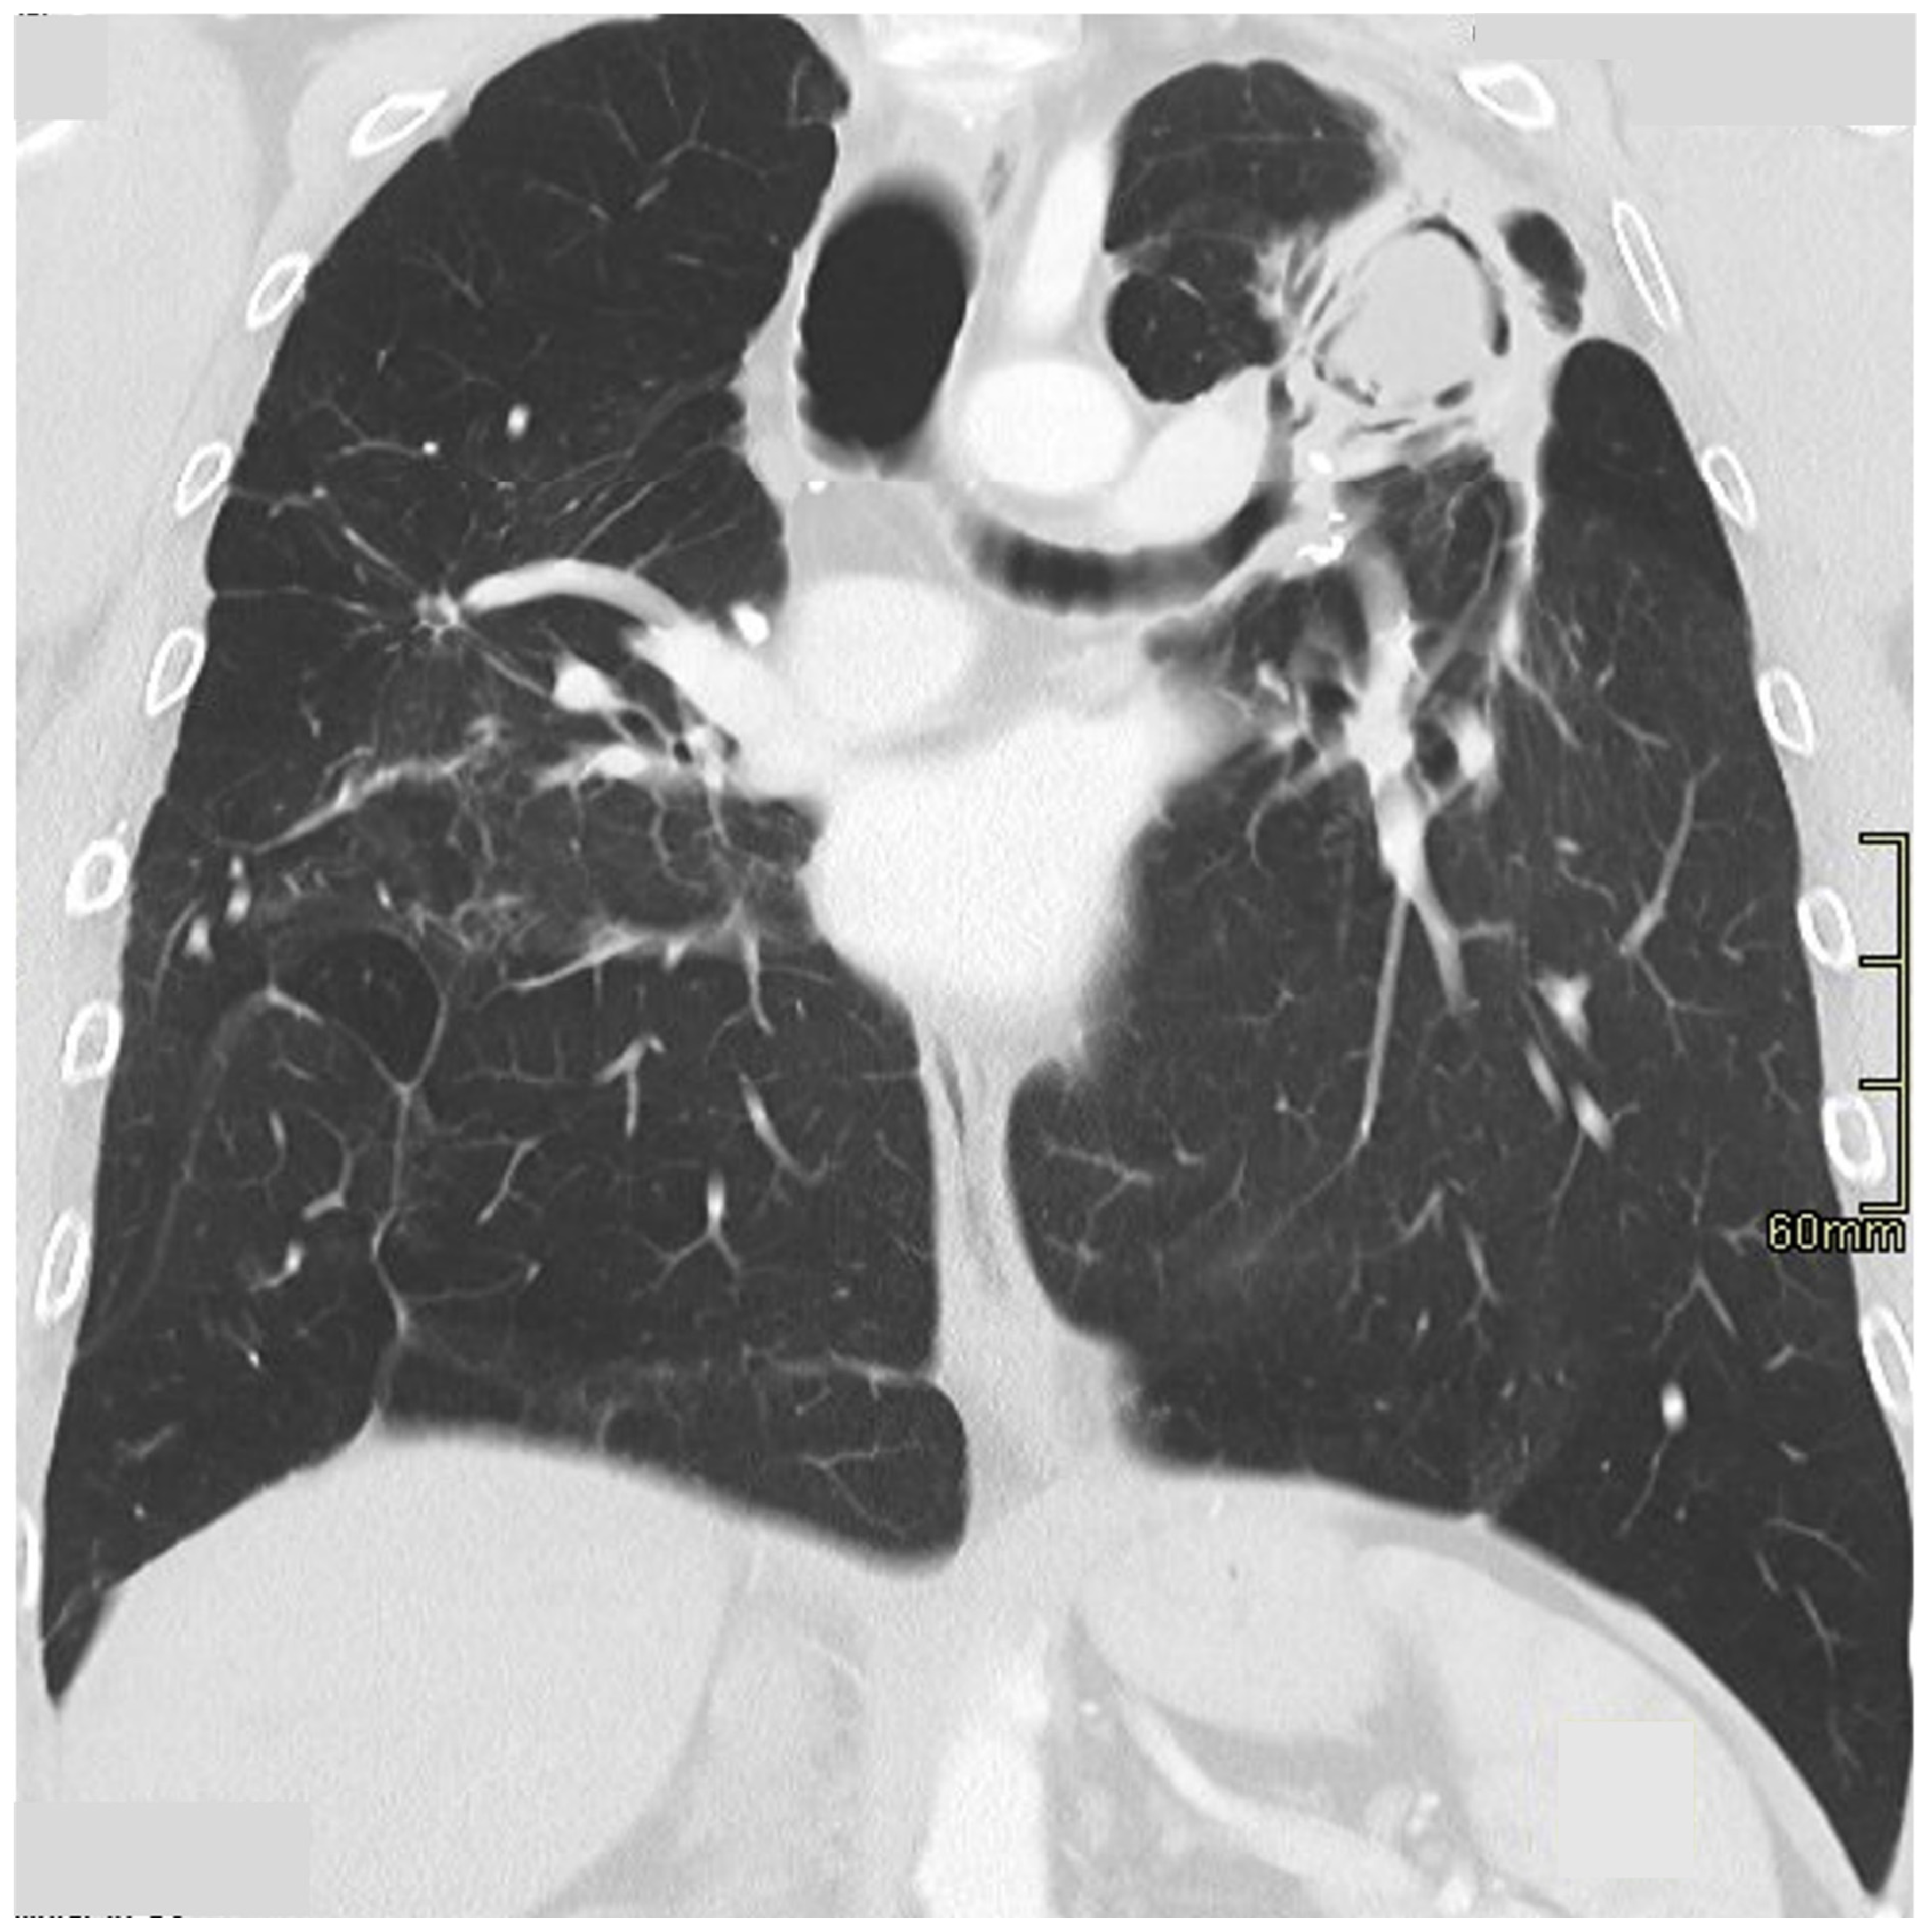

3.6. Pulmonary Fibrosis

Pulmonary fibrosis develops in 20–30% of patients [13,72]. The typical CT manifestations include coarse linear opacities, bronchocentric reticulation causing volume loss in the upper lobes and classical posterior retraction of the central bronchovascular structures [48,58] (Figure 6). Encasement of the bronchovascular bundles with conglomerate fibrosis masses may occur, with bronchial distortion and traction bronchiectasis/bronchiolectasis [10,47,73]. Honeycombing is seen in a significant minority and, in contrast to idiopathic pulmonary fibrosis (IPF), has a predilection for the mid-to-upper zones [10,74]. That said, in some patients, sarcoidosis does appear to masquerade as IPF on CT with basal predominant reticulation, ground-glass opacification and interlobular septal thickening [75]. In a recent study by Collins et al., 25 patients with combined sarcoidosis and IPF were reviewed [76]. Interestingly, the diagnosis of sarcoidosis was made, on average, a decade earlier than IPF; in 68%, sarcoidosis had been diagnosed on histopathologic examination at the time of IPF diagnosis. More importantly, survival in patients with combined disease was comparable to patients with classical IPF. Reports such as this raise the question of whether patients with combined disease represent a novel sarcoid phenotype or simply reflect a chance association (i.e., with IPF developing in patients with established sarcoidosis) [77].